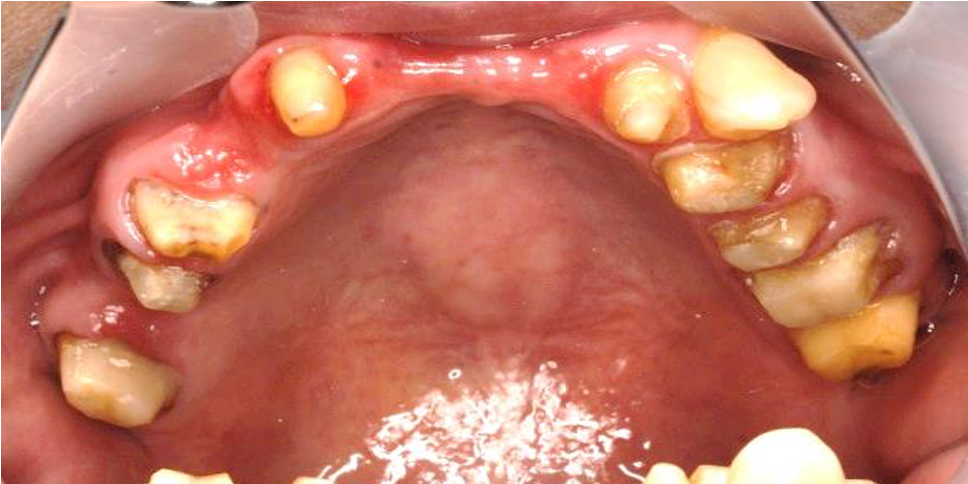

術前

ご来院いただいたときには、複数の欠損があるのと同時に重度の虫歯が進行していました。